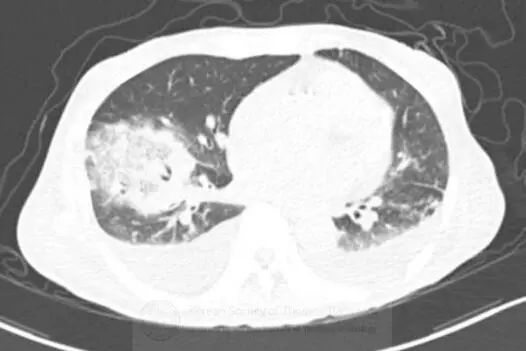

图1胸片示右肺下叶空洞性实变和左肺下叶实变。CT示右肺下叶类圆形实变伴中央磨玻璃影(反晕征),和空洞性病变。可见双侧胸腔积液。